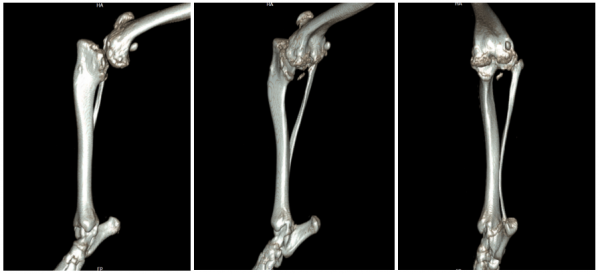

위에 사진에서 뒷다리의 무릎 아래쪽에 있는 길다란 뼈가 바로 경골입니다.

경골의 형태는 정상적으로 위의 사진과 같은 형태로 보여집니다.

수술 전에는 CT 촬영을 통해 방사선(X-ray)으로는 확인할 수 없는

정교한 뼈 구조와 관절면의 위치를 세밀하게 분석했습니다.

그 결과, 관절면의 접촉 부위가 한쪽으로 치우쳐 있는 것도 확인되었습니다.